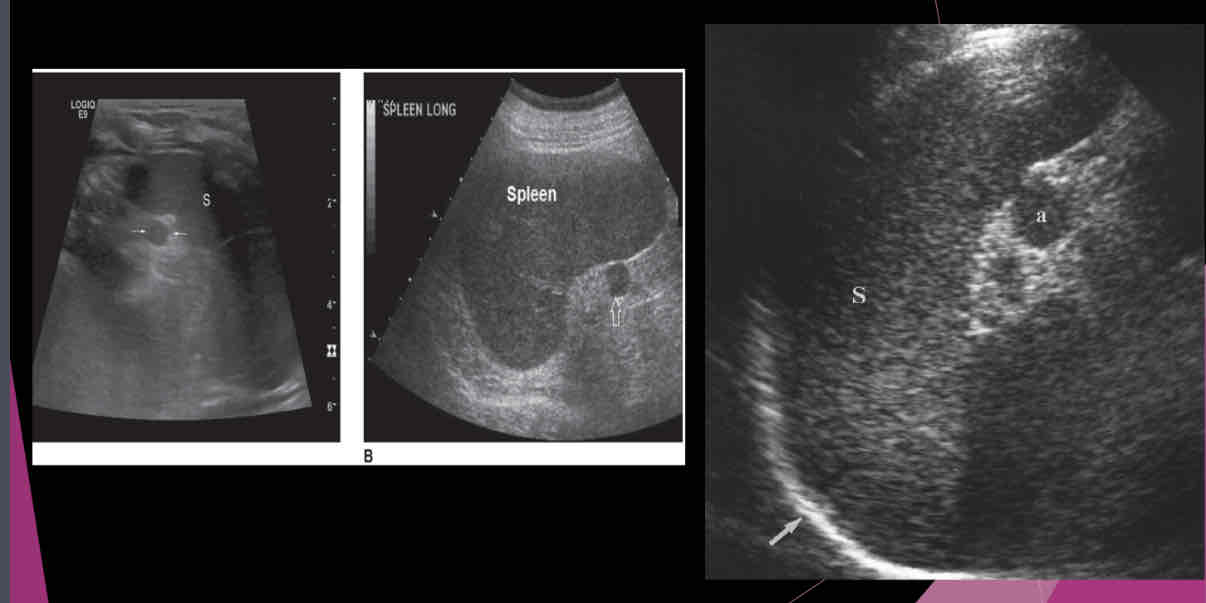

Describe the spleen on US?

-Homogeneous texture

- Echogenicity the same as or slightly below the normal liver echogenicity

- Smooth border at diaphragm

- Intercostal coronal view used to obtain spleen length

- Average length 11-13cm; usually decreases in size with age

- Usually 2/3 size of the liver

- Deep inspiration usually necessary to evaluate the entire organ

What is a relatively common anatomic variant?

accessory spleen (Splenule)

Most accessory spleens are small and measure between…

1.5 and 2.0 cm

An accessory spleen or splenule is _______ to spleen

hypoechoic

Isoechoic

hyperechoic

heterogeneous

Isoechoic